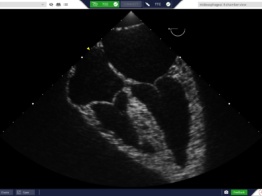

HeartWorks

A globally recognized cardiac learning platform, with simulation in cardiac anatomy, transthoracic, transesophageal echocardiography (TTE/TEE) and live 3D echocardiography. Ideal for programs prioritizing realistic cardiac anatomy and pathology.

Real Ultrasound Data

TTE, TEE & Live 3D Echo